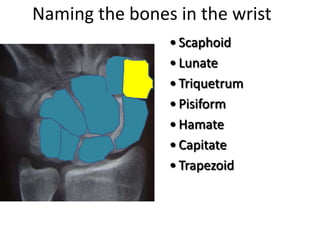

- Naming the bones, joints, tendons, nerves and skin landmarks of the hand and wrist.